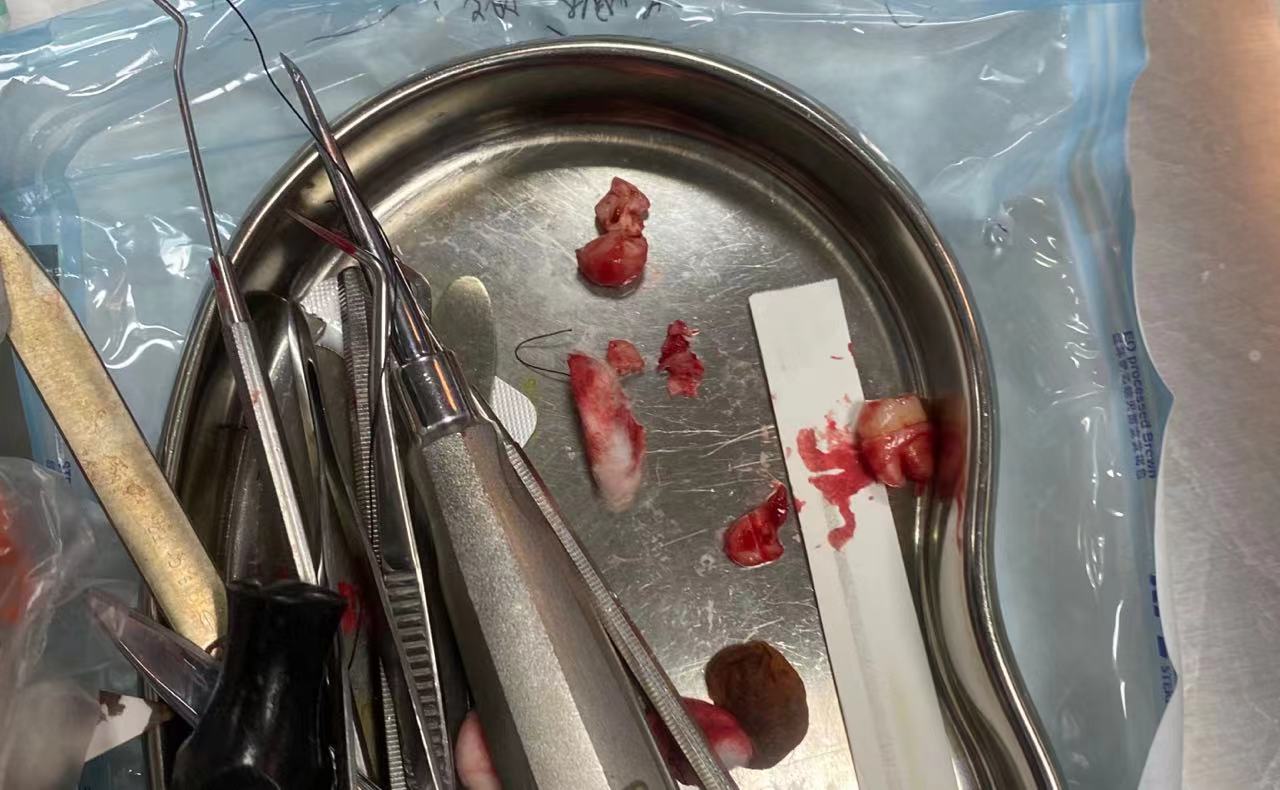

牙齿照片,血腥慎点

术后给了我冰袋消肿,拔完牙后一小时就吃了消炎药和布洛芬,怕疼的厉害。两小时后,麻药逐渐褪去,但感觉也没有想象中的那么疼,但是进食还是有点困难,只吃了点面包就睡了。第二天起来,上嘴唇意料之中地肿了,但是还好。不过最难受的是由于缝针的线头在上嘴唇内侧的牙龈上,这些线头磨我嘴唇导致了口腔溃疡,太难受了,不过过了三天左右逐渐好转了。

之后的三颗智齿就很顺利了。一周后去医院拆线,然后就是拔了左边边上下两颗阻生智齿,过程还是很顺利的,上牙还是他的学生拔的,下牙由于不太好拔,刘教授把牙齿分开了两半,用了很大的力气才顺利拔出。第二天进食吞咽还是有点疼痛,不过过几天就好了。第三次拔了右边一颗水平阻生,挺顺利的,第二天吃东西居然不疼还没有肿,当天晚上还吃了麦当劳。(可能是身体以及适应了这种疼痛。)